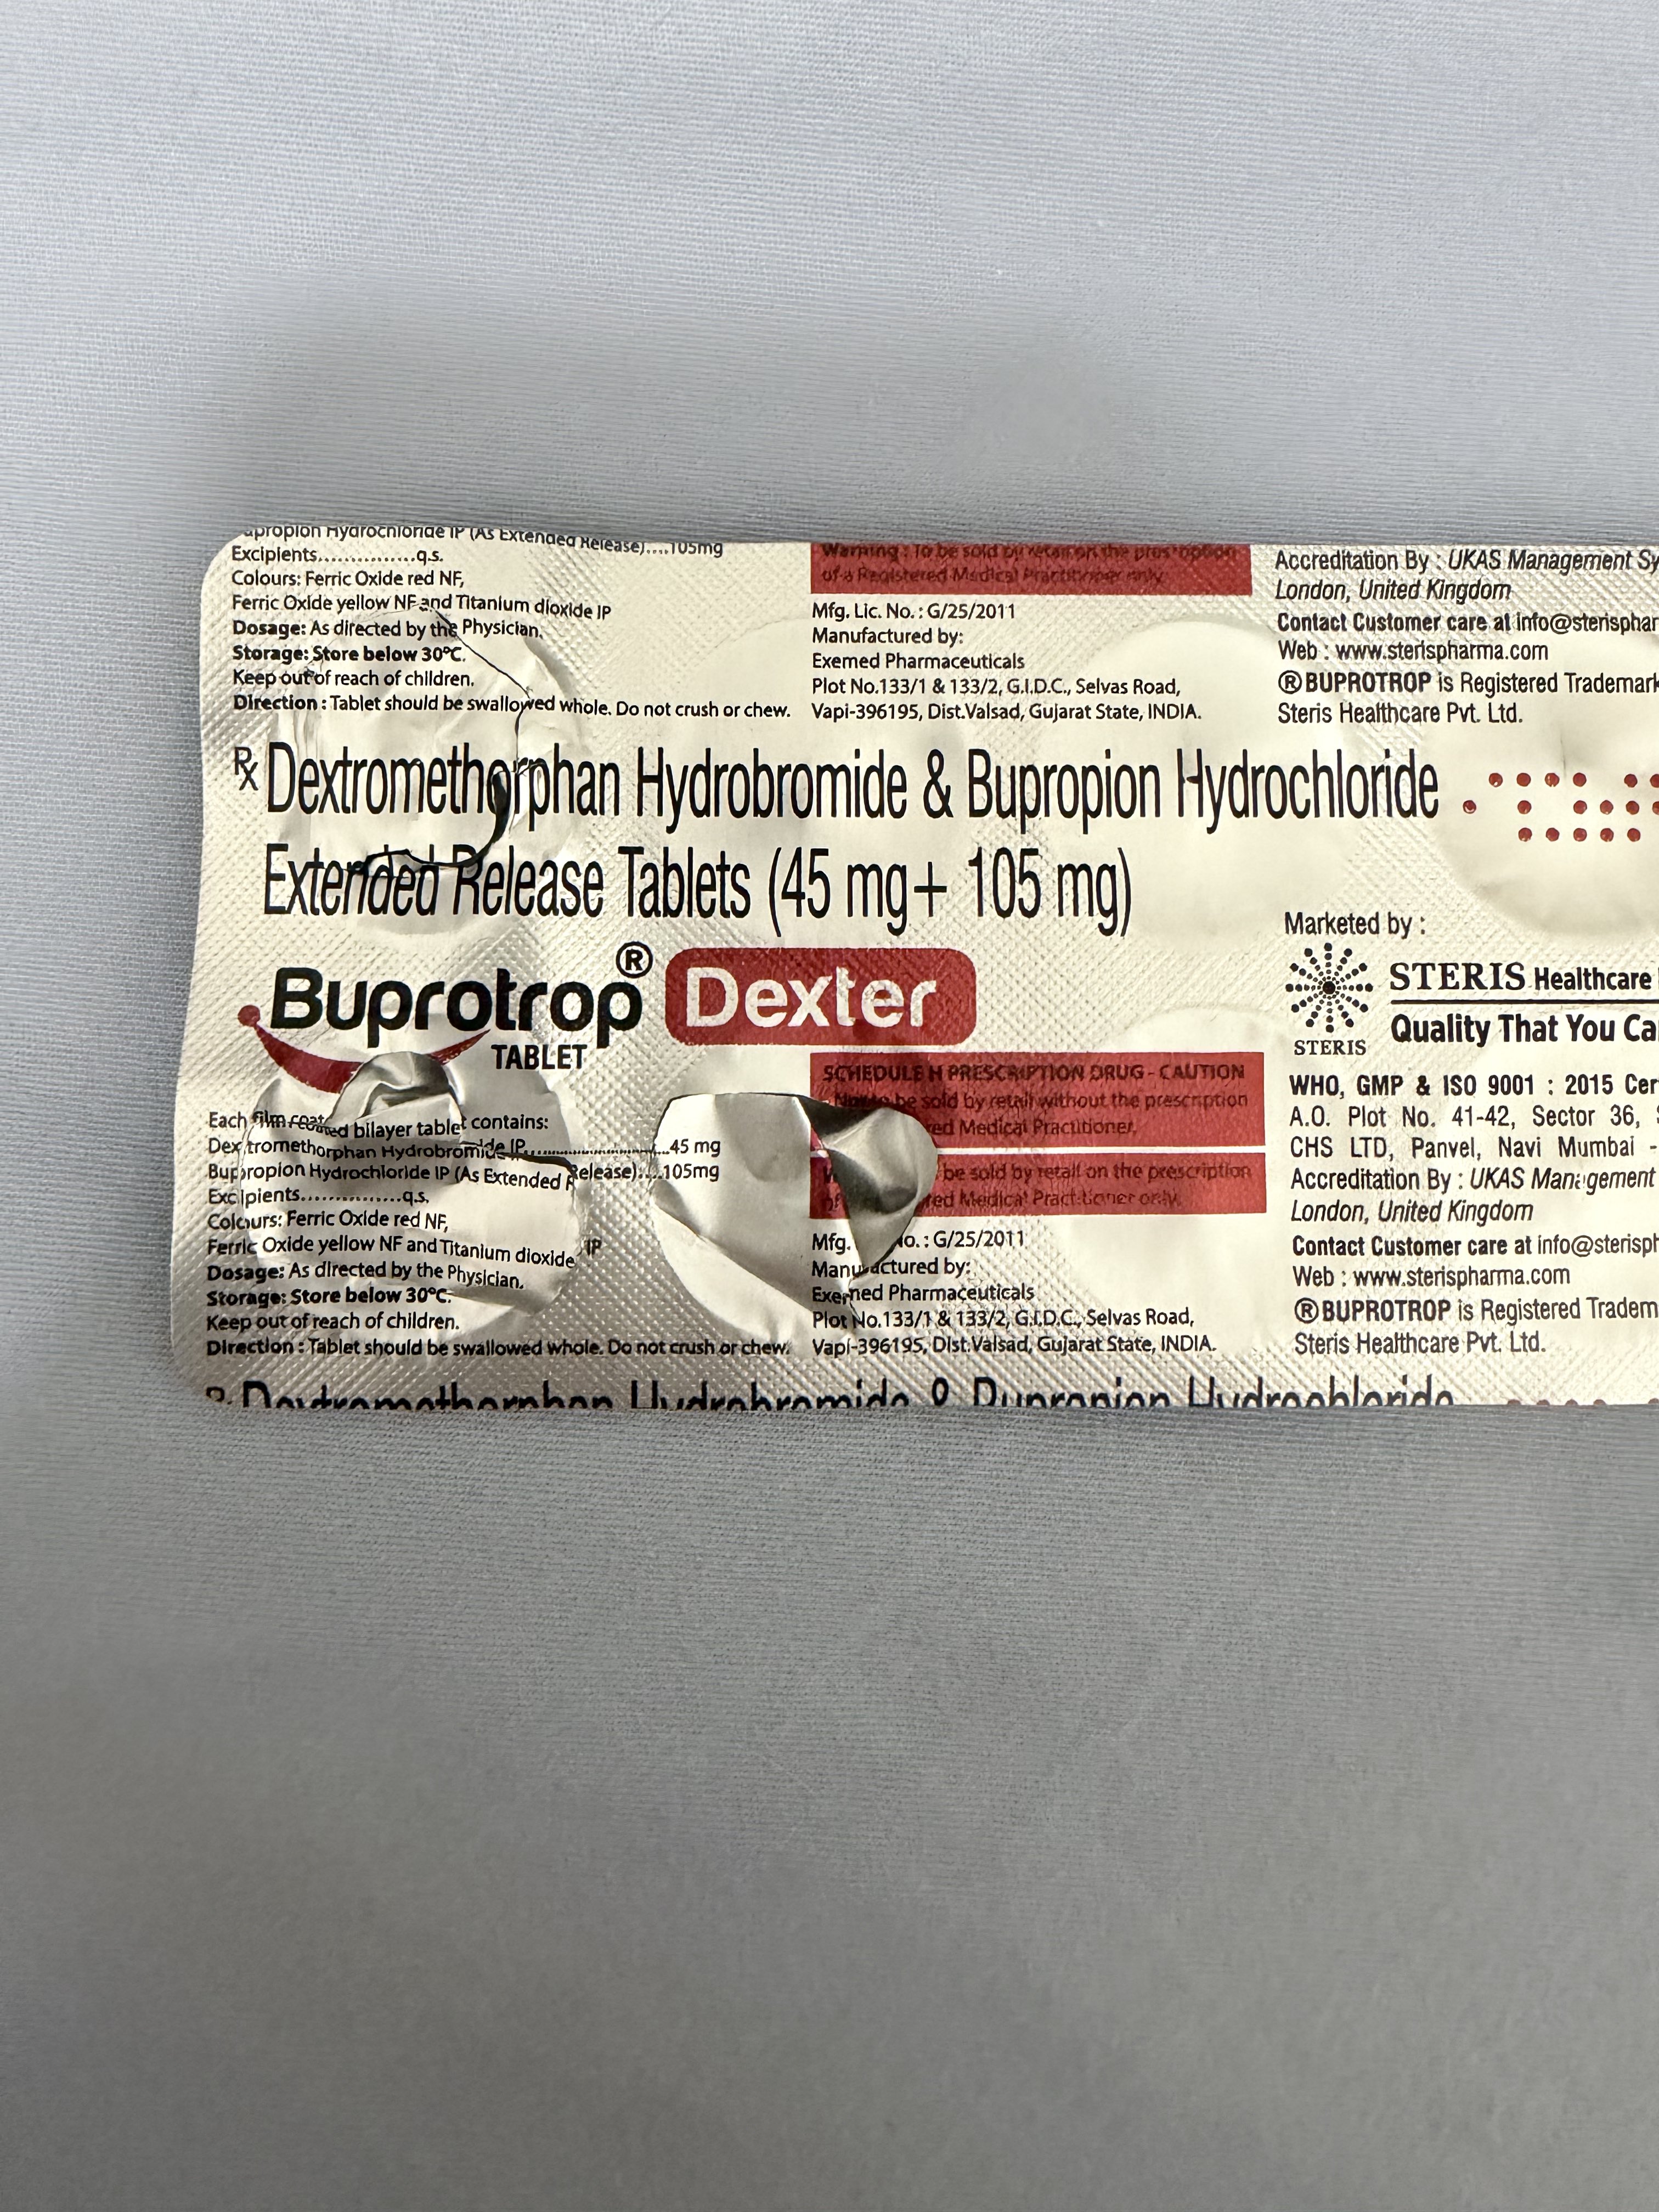

看上去像是为了描述某类特定效应而创造的术语(可能是nmda受体活性增强),用来对抗因NMDA受体拮抗剂(比如氯胺酮、DXM、PCP等)引发的解离体验(dissociation)。

看上去像是为了描述某类特定效应而创造的术语(可能是nmda受体活性增强),用来对抗因NMDA受体拮抗剂(比如氯胺酮、DXM、PCP等)引发的解离体验(dissociation)。